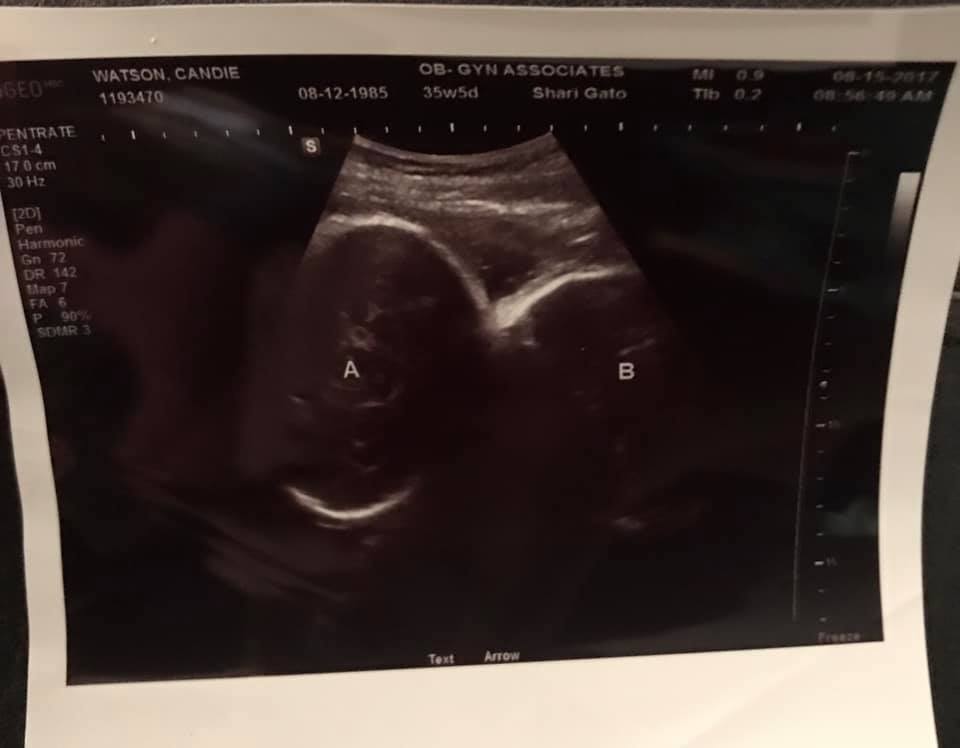

- Ultrasound Photos at 35 Weeks Pregnant With Twins

Ultrasound Photos at 35 Weeks Pregnant With Twins